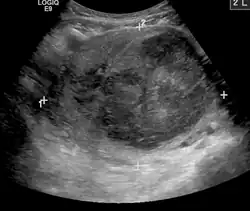

A very large (9 cm or 3.5 in) fibroid of the uterus causing pelvic congestion on US

Chronic pelvic pain

• Veins have one-way valves that help blood flow toward the heart. If the valves are weak or damaged, blood can pool in veins, making them swell. When this happens near the pelvis, it is called pelvic congestion syndrome, which can lead to chronic pain beneath the level of the belly button.

• Pelvic congestion syndrome usually affects women who have previously been pregnant, because the ovarian veins and pelvic veins had widened to accommodate the increased blood flow from the uterus during pregnancy. After the pregnancy, some of these veins remain enlarged and fail to return to their previous size, causing them to weaken and allowing blood to pool.[42]

• An interventional radiologist can offer a minimally invasive treatment option for pelvic congestion syndrome: ovarian vein embolization

• Ovarian vein embolization is a same-day treatment which takes place in an interventional radiology suite. The interventional radiologist gains access through a large vein in the groin, called the femoral vein, by using a small catheter, which is a flexible tube like a strand of spaghetti. The catheter is moved through the vein to the enlarged pelvic veins, allowing the introduction of embolic agents, which are medications that cause the vein to seal off and relieve the painful pressure.[43]

• This treatment can be less expensive than surgery and is much less invasive.

• A number of diagnostic tests can be performed through minimally invasive methods, to determine whether a patient's chronic pelvic pain is a result of pelvic varicose veins. These tests include:

• Pelvic and transvaginal ultrasound

• Pelvic venogram

• Computed tomography (CT)

• Magnetic resonance imaging (MRI)